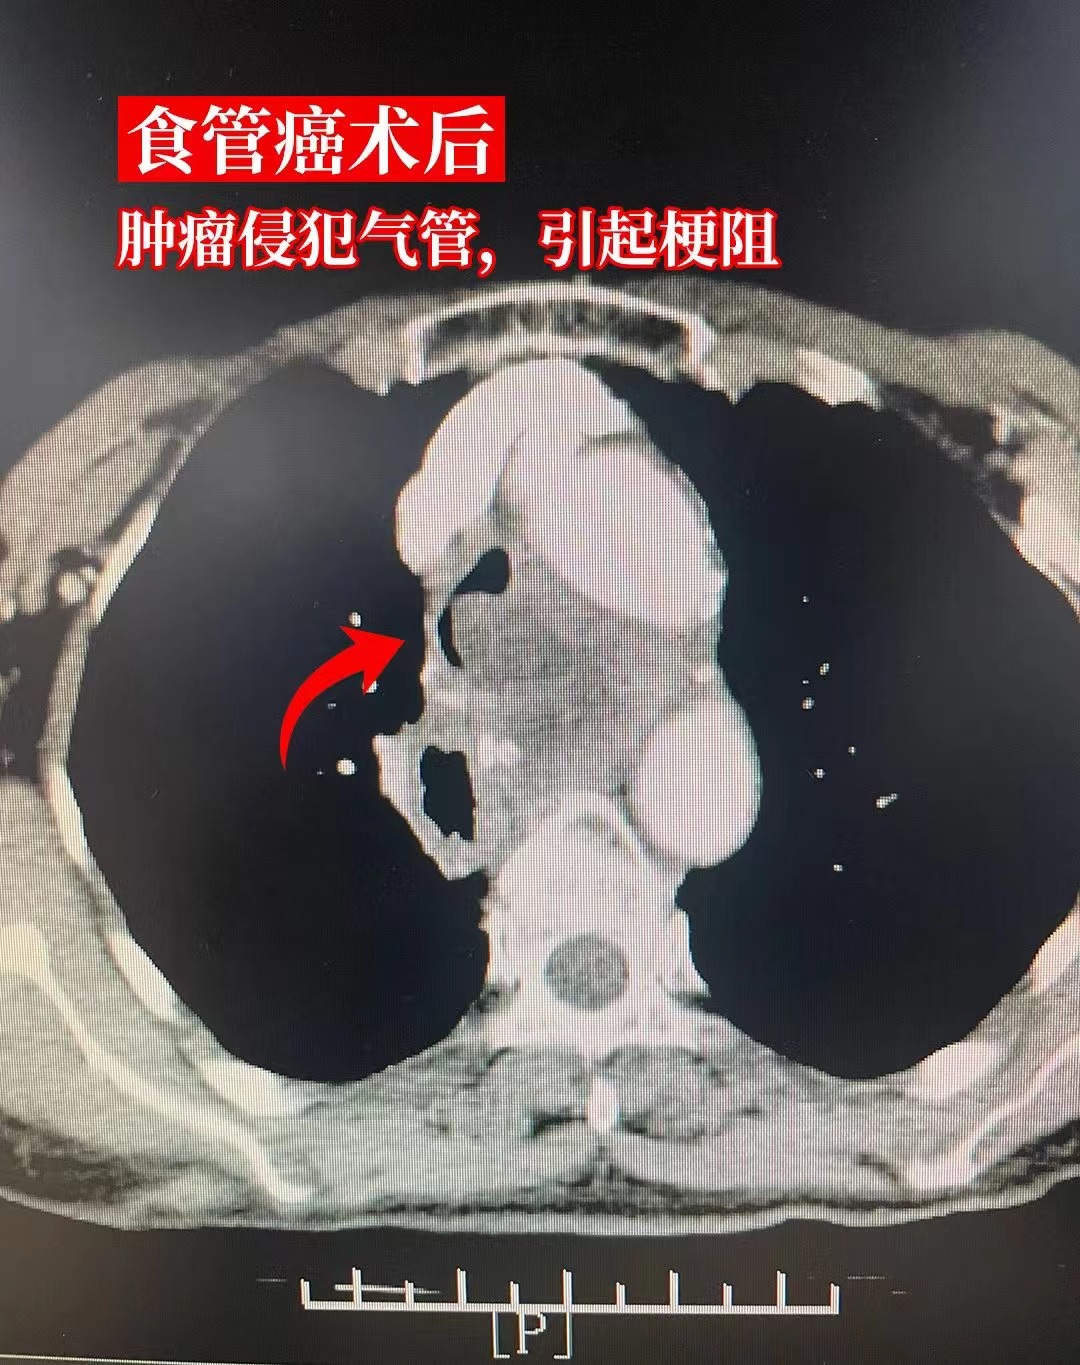

3、食道癌晚期患者的生存时间一般为几个月到一年左右,但具体时长因人而异其生存期主要受以下因素影响癌症的严重程度晚期食道癌通常已扩散至食管周围组织或远处器官如肝脏肺等扩散范围越广侵犯器官越多,生存时间可能越短例如,仅局部淋巴结转移的患者生存期可能长于多器官转移者患者的整体健康状况基础疾;食管癌中晚期患者的存活时间通常在数月到数年之间,具体因个体差异而异其影响因素主要包括以下三方面1 肿瘤分期食管癌的分期依据肿瘤大小侵犯深度淋巴结及远处器官转移情况划分中晚期通常指肿瘤已穿透食管壁深层组织,并可能转移至邻近淋巴结或肝肺等器官此类患者预后较差,晚期患者5年生存率。

4、食管癌晚期患者的存活时间因个体差异而异,主要取决于疾病分期和恶性程度,无法一概而论以下是关于食管癌晚期存活时间的具体说明未积极治疗的情况食道癌晚期的病人,如果不进行积极治疗,生存时间一般是36个月左右积极治疗的情况如果能够采取积极的治疗措施,如联合化疗放疗靶向药物治疗生物;食道癌晚期患者的生存时间因人而异,通常在三个月到六个月不等,但具体时长受多种因素影响多发远处转移是影响生存时间的关键因素之一当食道癌晚期患者出现肝肺骨等多器官转移时,肿瘤负荷加重,身体机能迅速下降,此时生存期可能缩短至三个月到六个月但需注意,这一范围并非绝对,部分患者可能;食道癌晚期患者的生存期需根据具体治疗情况判断积极治疗的情况下若患者接受规范的综合治疗如手术化疗放疗靶向治疗或免疫治疗等,5年生存率可达30%左右部分患者通过个体化治疗和定期随访,生存期可能超过5年治疗的有效性取决于肿瘤分期病理类型患者身体状况及对治疗的反应例如,局部。